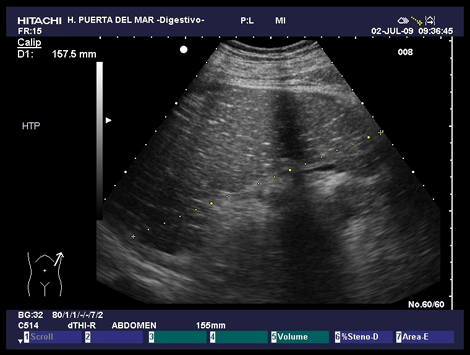

Esplenomegalia con pequeños focos hiperecoicos asociada a hipertensión portal Dra. Paloma Rendon Unceta |